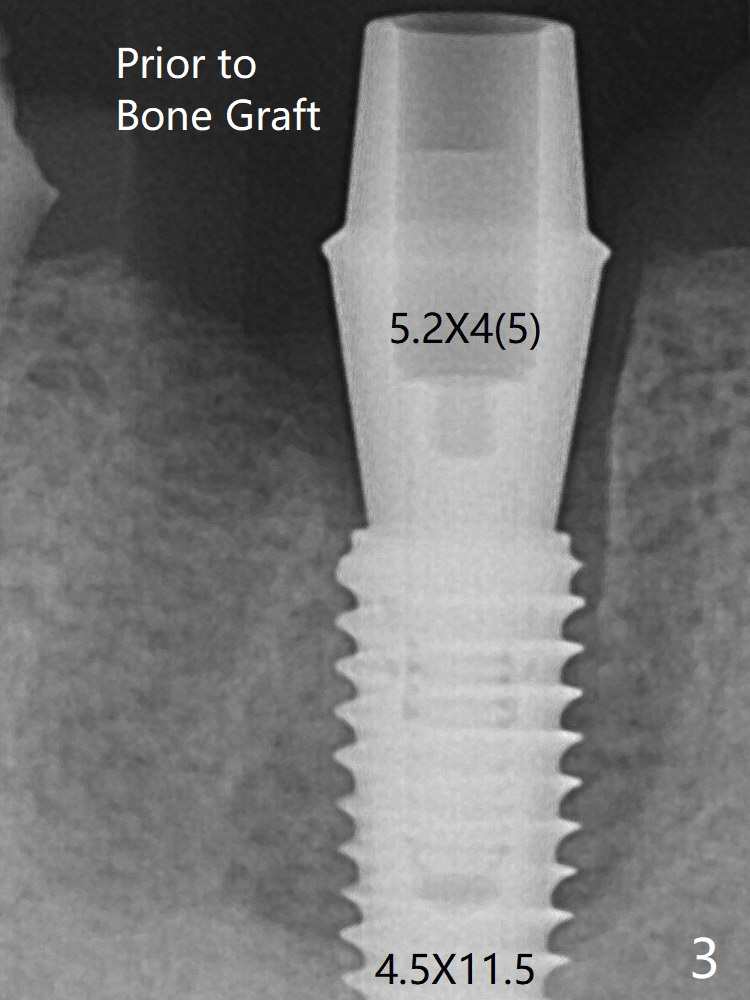

Mixture of cortical bone (125μm – 850μm) and cortical/cancellous bone (.5-1 mm) with PRF (sticky bone, B in Fig.6). There is not enough bone coronal to the implant plateau 2 months post graft (Fig.12). Three months later, bone graft will be re-placed possibly with uncover.